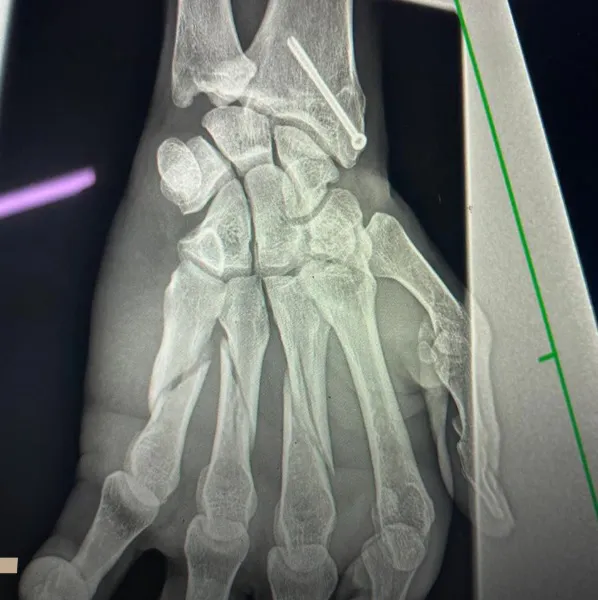

Adolfo Cambiaso se coronó en el Abierto Británico con su hija Mia, pero terminó con tres dedos fracturados

En cuanto a su complicación, no se confirmó el tiempo que deparará su recuperación. Los médicos son optimistas y esperan que pueda empezar a entrenar de cara a los campeonatos de la Triple Corona 2025, que ya fueron confirmados entre septiembre y diciembre: el 132º Abierto de Hurlingham (del 23/9 al 4/10), el 85º Abierto de Tortugas Country Club (del 7/10 al 25/10) y el 132º Abierto Argentino de Polo, en la mítica cancha de Palermo, del 31/10 al 6/12. La gran novedad pasa con la presencia del equipo La Natividad-La Dolfina, una de las uniones más llamativas para este año.